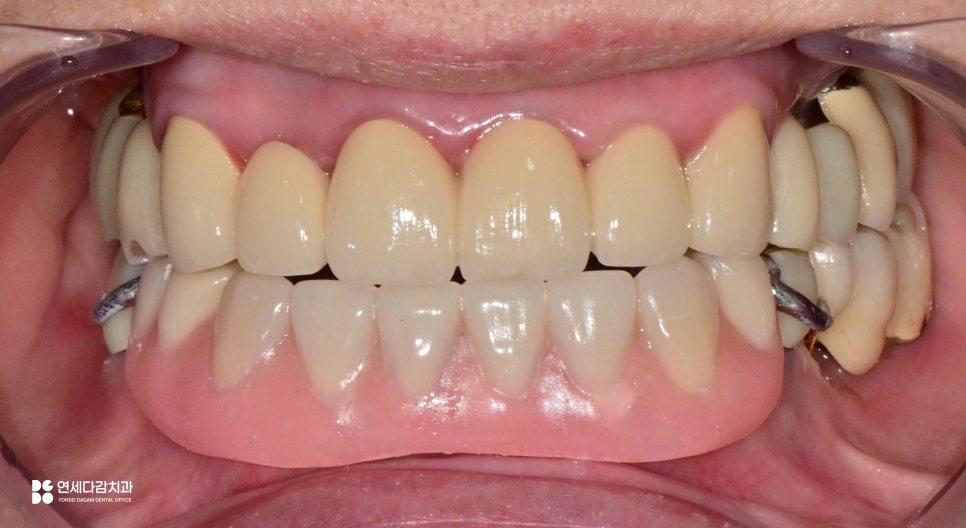

먼저 술전 사진을 확인해 보면,

아랫니들은 충치로 파절이 되어 있습니다.

치관은 이미 손상되어 남지 않았으며,

치아 뿌리만 확인되는 부위도 있습니다.

이렇게 치관이 없고 치근만 남은 경우를

잔존 치근이라고 부릅니다.

치관이 없으니 기능을 할 수 없고,

잇몸 아래 남아 있는 잔존 치근들은

염증과 감염의 원인이 될 수 있어

발치는 불가피한 상황입니다.

이렇게 개인에게 맞게 제작된

보철을 통해 심미, 기능성은 회복됩니다.